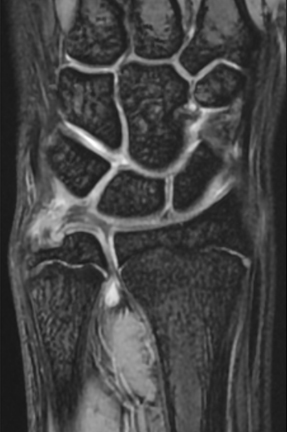

単純X線の他、MRI、手関節造影/CTを行います。単純X線では、TFCC自体は映りません。しかし、骨形態の評価、とくに突き上げ症候群の評価に有用であり、必須の検査の1つです。MRIではTFCCの損傷の有無を評価します。また、ECU腱鞘炎などその他の障害/疾患の有無を確認します。しかしながら、MRIではTFCCの詳細な評価が難しい場合があり、手関節造影/CTが必要となることがあります。手関節造影/CTでは、造影剤を橈骨手根関節内および遠位橈尺関節内に注入しTFCCの円盤部や末梢部、表層部、および小窩(Fovea)部などでの断裂形態を確認します。その他、手根骨間靱帯損傷や手関節尺側部の骨形態について評価します。

【MRI】

【手関節造影】

【手関節造影後CT】